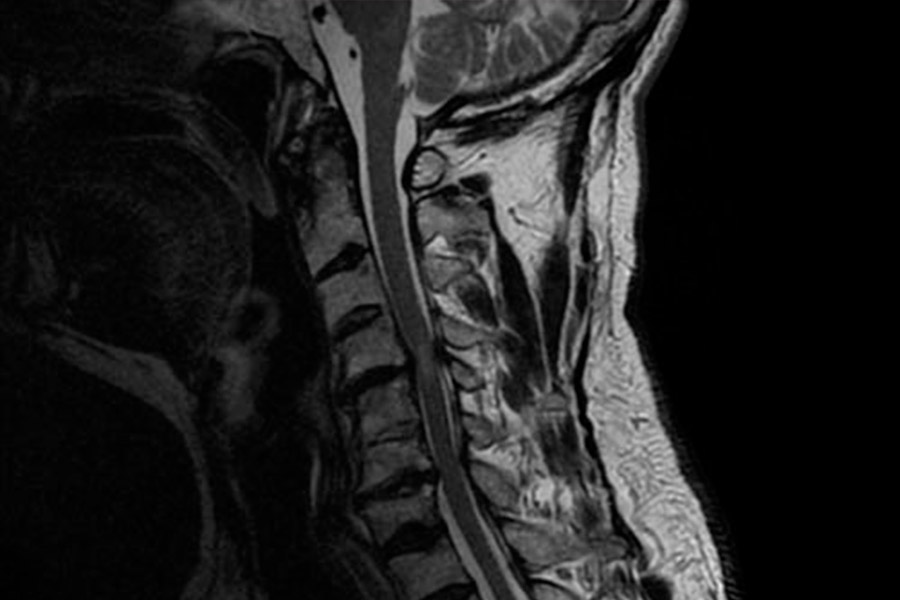

En este caso clínico, los especialistas del Instituto de Cirugía Avanzada de Columna intervienen a una paciente joven mediante artrodesis cervical.

La paciente presenta varias hernias discales cervicales, empeoradas por la presencia de artrosis en la zona y que provoca dolencias en el lado derecho (brazos y cuello).